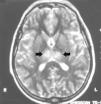

Figura 1. Imagen potenciada en T1, hiperdensidad en seno longitudinal superior, recto trasverso y sigmoideo izquierdo.